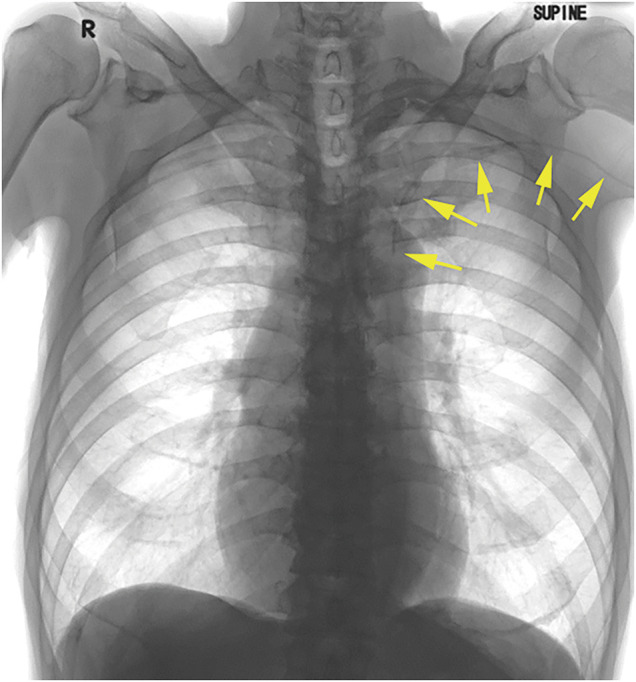

Case presentation: A 75-year-old male patient required a central venous port for chemotherapy and radiation therapy for mid-thoracic esophageal cancer. Preoperative computed tomography images revealed that the PLSVC ran ventrally to the aortic and left pulmonary arteries, directly communicating with the right atrium. A peripherally inserted central catheter (PICC) port was planned. The catheter tip of the PICC port was placed within the left superior vena cava instead of the more common right superior vena cava, because the appropriate vessels could not be identified in the right upper arm. This anomaly necessitated a review of findings on the preoperative imaging and underscored the importance of early detection through echocardiography and radiographic guidance to prevent procedural complications. Reconstructed three-dimensional images and radiography-guided catheterization support the navigation of PICC port insertion.